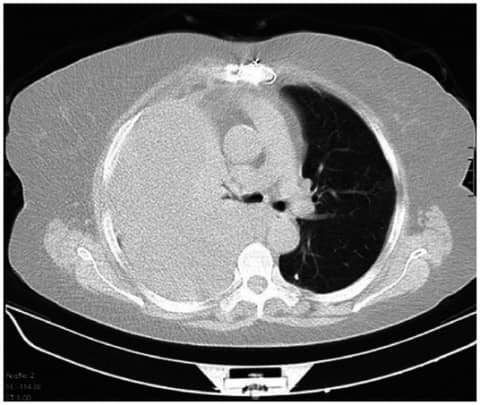

Hemothorax is a collection of blood in the thoracic cavity. Many times, this occurs in the setting of chest trauma, either penetrating (i.e., gun shot wounds) or blunt (i.e., a car accident). When a significant collection of blood occurs in the chest, it is drained many times by insertion of a tube in the chest.

The conventional wisdom is that this tube should be large, so that the blood can drain easily, and the blood does not clog the tube. Yet, many studies have shown that smaller tubes can do just as well. Yet, is this actually the case in the literature?